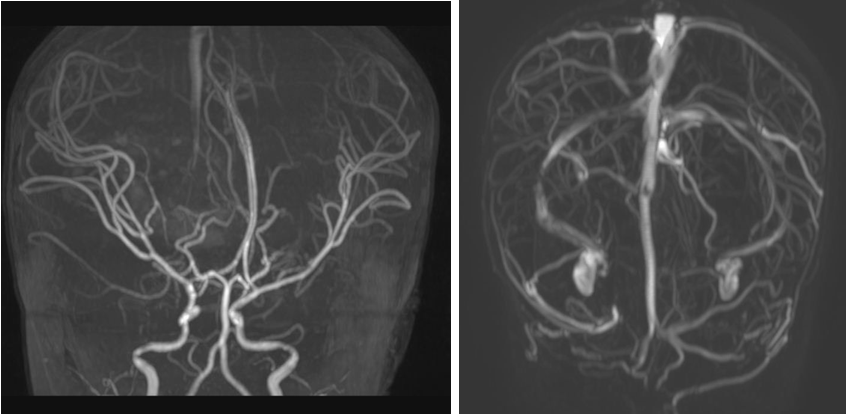

术前影像

术前颅脑MRA、MRV